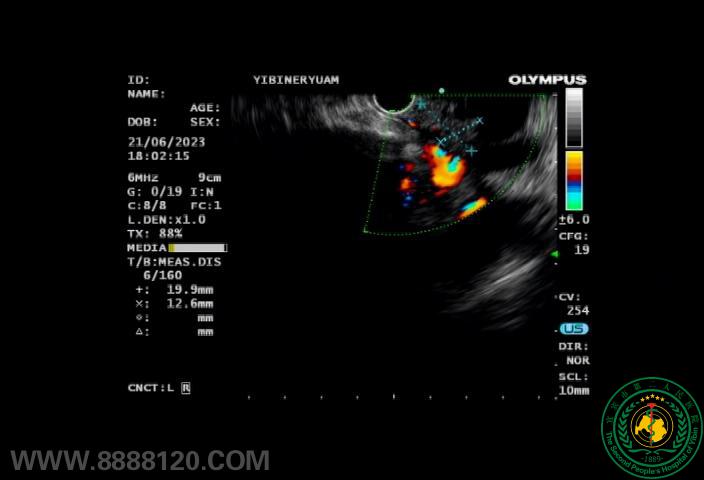

案例一:患者68岁男性,因“持续性上腹疼痛16天”入院。入院后查胰腺炎及肿瘤标志物均正常,磁共振CT均提肝内外胆管及主胰管扩张,没有发现明确占位病变超声内镜检查发现了一个大小约1.9×1.2cm的胰腺微小肿瘤。

超声内镜